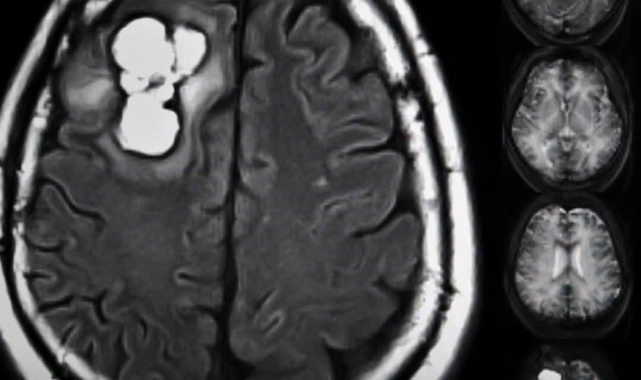

Glioblastomun Zayıf NoktasıNormal beyin hücreleri enerjilerini glikozdan alarak beyin fonksiyonlarını sürdürürken, glioblastom hücreleri şekeri yalnızca enerji için değil, aynı zamanda hızlı çoğalma ve doku istilası için yapı taşı olarak kullanıyor. Bilim insanları, bu tümörlerin özellikle serin ve glisin gibi amino asitleri içeriden üretmek yerine doğrudan kandan “çektiğini” ortaya koydu.Diyet Müdahalesi ile Yavaşlayan TümörlerAraştırma ekibi, fareleri bu amino asitlerden yoksun bir diyetle beslediğinde tümörlerin büyüme hızında ciddi bir yavaşlama gözlemledi. Ayrıca, bu beslenme düzeni uygulanan farelerin radyasyon ve kemoterapiye daha iyi yanıt verdiği bildirildi.Yeni Tedavi UfuklarıÇalışmayı yürüten ekip, bulguların glioblastom tedavisinde beslenme temelli ek tedavi yöntemleri için yeni kapılar açabileceğini belirtiyor. Özellikle serin ve glisin gibi amino asitlerin sınırlanmasının, gelecekte mevcut tedavilere destekleyici bir strateji haline gelebileceği vurgulandı.